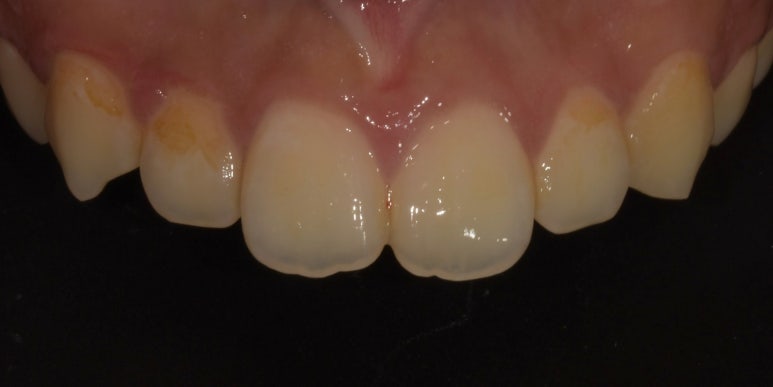

법랑질성형 환자 시술 전 모습

앞니 2개 끝부분이 울퉁불퉁한 모습을 확인하실 수 있습니다.

설명만 들어서는 별 것 아닌 것 같아보여도 막상 법랑질성형이 완료된 후에는 훨씬 더 라인이 부드럽고 깔끔하게 정돈된 모습을 확인하실 수 있습니다.

그럼 법랑질성형 시술 사례를 보실까요?

법랑질성형 시술사례

사진을 보시면 법랑질성형 후 날카로웠던 부분 및 앞니 2개의 끝부분이 다듬어져

훨씬 깔끔하고 정돈된 느낌이 드는 것을 확인하실 수 있습니다.